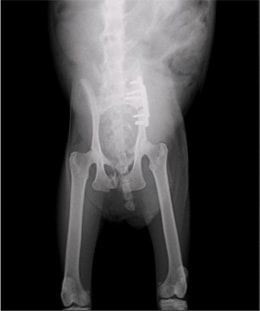

症例:交通事故による椎体脱臼

柴犬:9歳、避妊雌

交通事故直後、胸腰部に激しい疼痛、両後肢に完全麻痺を認め、シェフシェリントン徴候を呈していました。レントゲン検査において、第11-12胸椎間の脱臼が認められました。

脊髄の減圧、脊柱管の再構築・安定化を目的に、片側椎弓切除術およびMatrixMANDIBLE Plateによる椎体固定を実施しました。

隣接椎体を架橋するようにプレートを設置しました。

術後レントゲン写真